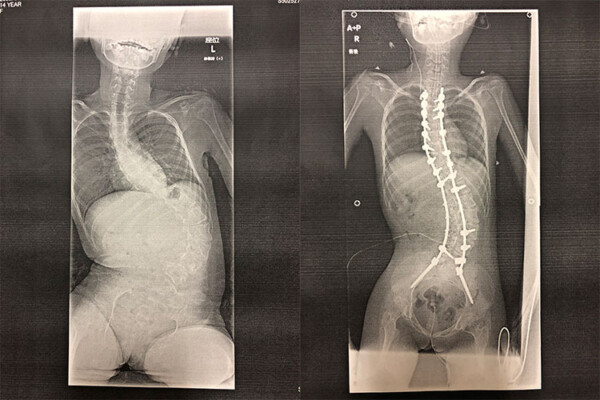

レット症候群は、1万人〜1.5万人に一人の確率で、女の子に発症する難病です。遺伝子の突然変異で起こるといわれていて、生後半年〜1歳半までごく普通に成長していたのが、徐々にできないことが増えていく難病です。症状の幅は広いものの、ほとんどの子が言葉を発さず、てんかんや側弯症、睡眠障害や息堪えなどを併発します。